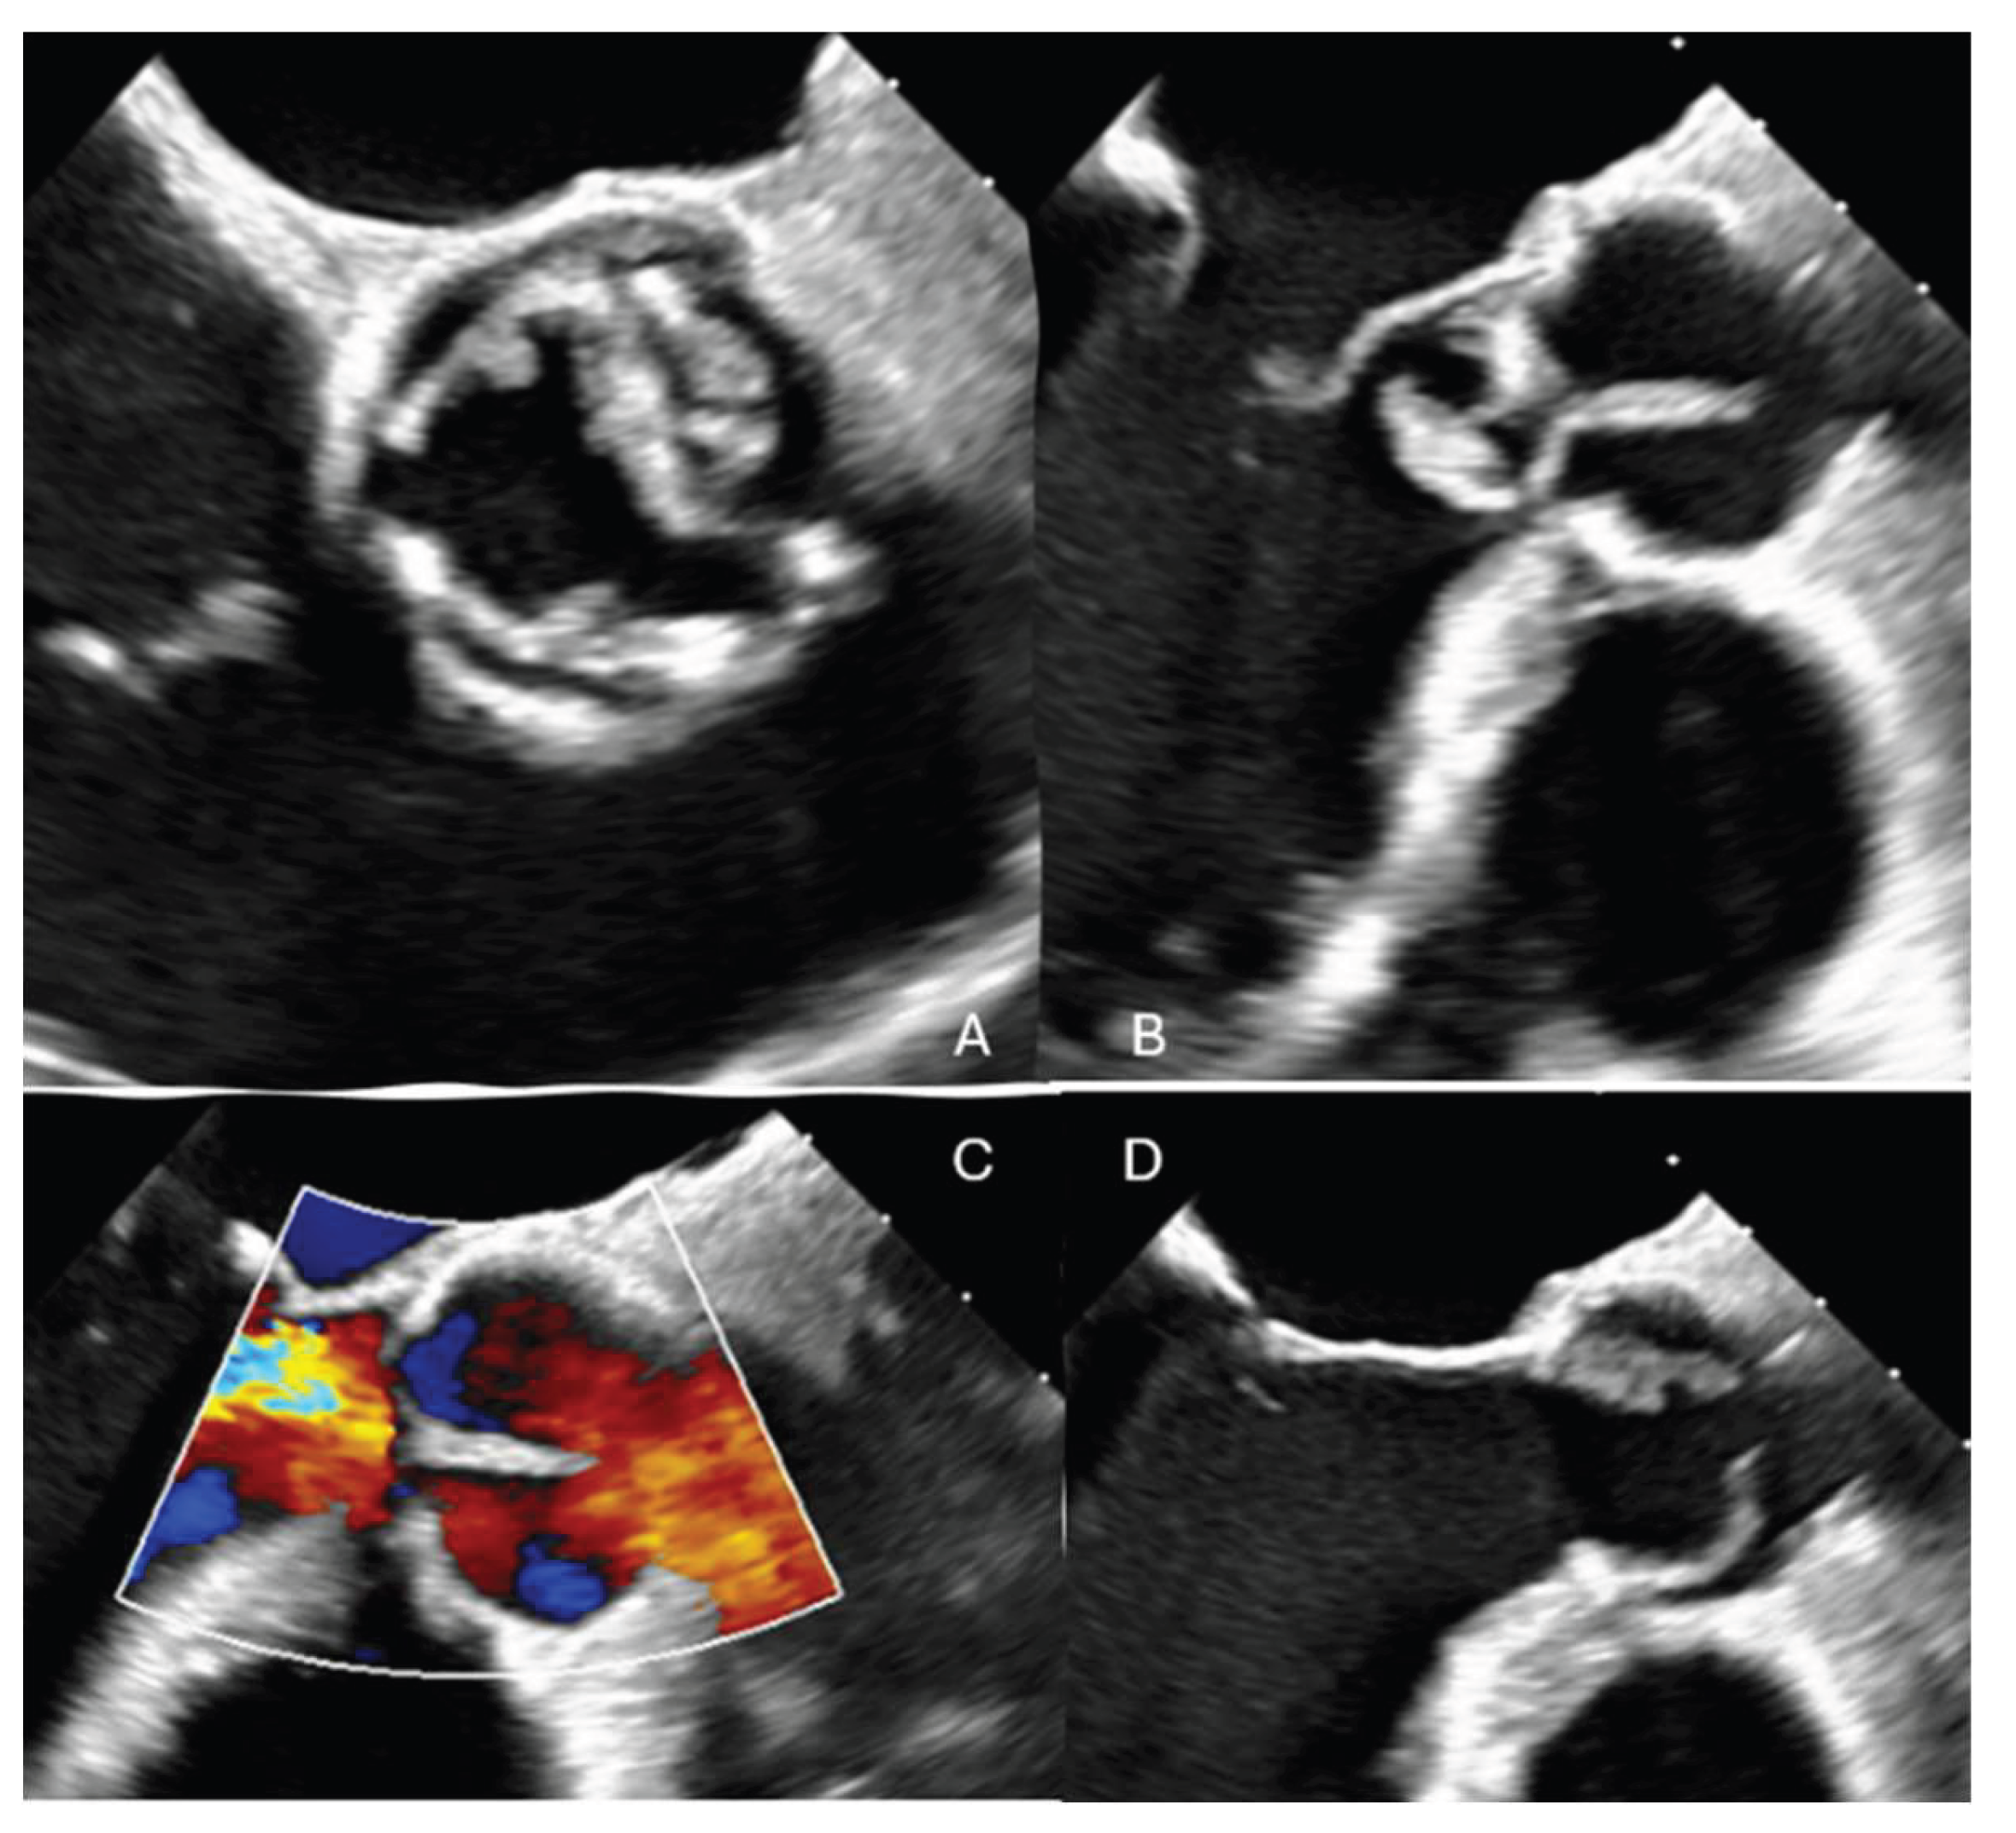

The patient experienced rapid clinical deterioration, progressing to multiorgan failure characterized by septic and cardiogenic shock, acute hepatic dysfunction (shock liver), acute renal failure, septic encephalopathy, disseminated intravascular coagulation, and new-onset atrial flutter. Despite a calculated in-hospital mortality risk of 89.5% based on the EuroSCORE II, the severity of the clinical scenario mandated immediate salvage surgery. A redo median sternotomy was undertaken in a technically complex setting, complicated by the absence of the pericardium and dense mediastinal adhesions from the previous surgery. Careful and meticulous dissection allowed for the safe identification of the great vessels. Central cannulation was achieved via the aortic arch for arterial return and bicaval venous access for drainage. Cardiopulmonary bypass (CPB) was initiated under normothermic conditions, ensuring adequate systemic perfusion. The aorta was cross-clamped, and a transverse aortotomy was performed. Myocardial protection was provided through the administration of cold blood cardioplegia directly into the coronary ostia, with repeated doses to maintain optimal myocardial preservation throughout the procedure. Intraoperative exploration revealed extensive destruction: the left neocuspidal leaflet was completely perforated, and a large, highly mobile vegetation was found on the ventricular aspect of the valve. Furthermore, a sub- annular abscess was identified, extending from the left–right commissure into both the left and right sinuses of Valsalva. Radical debridement of all infected and necrotic tissue was undertaken, with evacuation of purulent material. The abscess cavity was meticulously excised until only macroscopically healthy tissue remained. The resulting defect, involving the annular region and extending approximately one centimeter into both sinuses, was reconstructed using two layers of continuous 4-0 Prolene sutures. Given the fragility of the annular tissue and the extensive debridement required, the use of a conventional sutured bioprosthesis was deemed inadvisable. A medium-sized Perceval sutureless bioprosthetic valve was therefore selected and deployed successfully. The aortotomy was closed using the Blalock technique with two layers of 5-0 Prolene sutures. Weaning from CBP proved challenging due to biventricular dysfunction in the context of preoperative multiorgan failure. As a result, femoro-femoral veno-arterial extracorporeal membrane oxygenation (VA-ECMO) was instituted intraoperatively to provide circulatory support and facilitate end-organ recovery. The total cross-clamp time was 58 minutes whilst CBP time was 125 minutes. Hemodynamic stabilization was gradually achieved, and ECMO was successfully explanted after 5 days. The patient remained in the intensive care unit for three weeks, during which progressive clinical improvement was observed. Transthoracic echocardiography performed prior to ICU discharge demonstrated normal function of the implanted Perceval valve (Figure 2 and Figure 3), with no evidence of paravalvular leakage or residual vegetations. At three-month follow-up, the patient remained clinically stable, and repeat imaging confirmed preserved valve function without signs of recurrent endocarditis.

Figure 2. Post-operative TOE following cusp and vegetation excision, annular debridement, and implantation of a Perceval Sutureless valve, showing a well-seated prosthesis without any paravalvular leak.